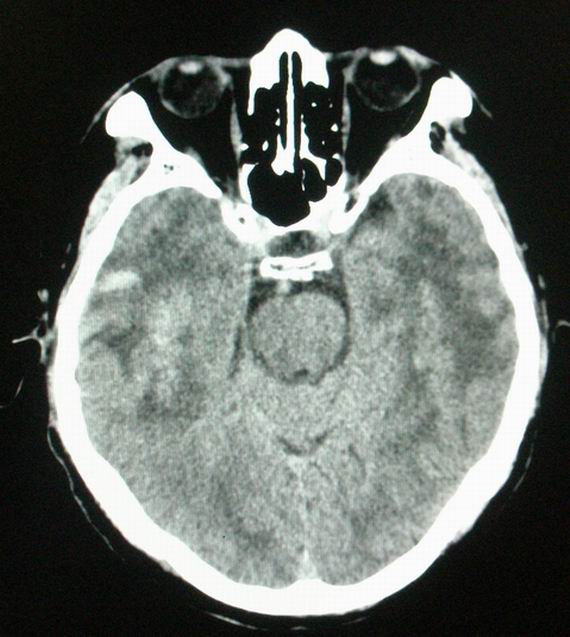

以下是引用随光逐影在2008-4-5 7:46:00的发言:[br]1)考虑为:多发性脑转移瘤。建议:行进一步检查。2)多发性腔隙性脑梗塞。3)脑白质病。4)脑萎缩。

以下是引用zjzjr在2008-4-5 9:00:00的发言:[br]1.双侧颞叶占位性病变,考虑为转移瘤可能性大。[br]2.左侧基底节区陈旧性腔隙性脑梗塞。[br]3.脑白质病。建议mri进一步检查。

以下是引用xuhuihong在2008-4-5 0:59:00的发言:[br]1.双侧颞叶占位性病变,考虑为转移瘤可能性大。[br]2.左侧基底节区陈旧性腔隙性脑梗塞。[br]3.脑白质病。建议mri进一步检查。

以下是引用形影不离在2008-4-4 23:29:00的发言:[br]1.双侧颞叶占位性病变,考虑为转移瘤可能性大。[br]2.左侧基底节区陈旧性腔隙性脑梗塞。[br]3.脑白质病。